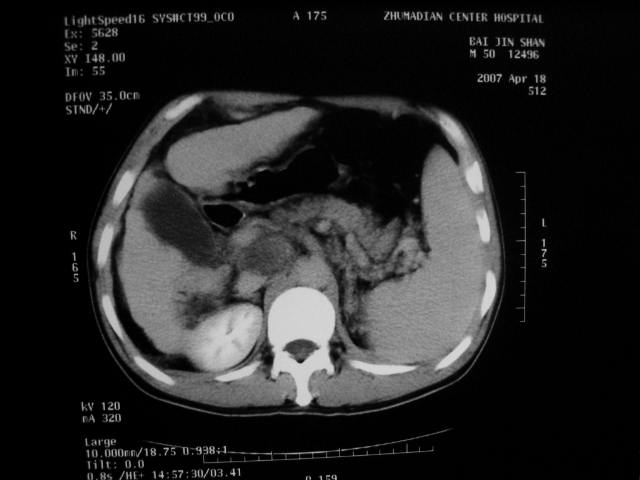

标题: CT7751:病人,50岁,肝硬化多年,行CT三期扫描 [打印本页]

标题: CT7751:病人,50岁,肝硬化多年,行CT三期扫描

动脉期病灶见轻度强化,考虑肝癌可能性大。

动脉期轻度强化 考虑 肝右叶小肝癌可能性大

肝硬化 脾大 胃底静脉曲张 肝癌 门腔间淋巴结肿大

肝硬化、脾大,静脉曲张,肝右叶低密度灶,增强无明显强化,还是考虑肝癌可能性大,建议结合afp检查。

考虑肝硬化,脾大,静脉曲张,肝右叶低密度灶,右肝癌可能性大。